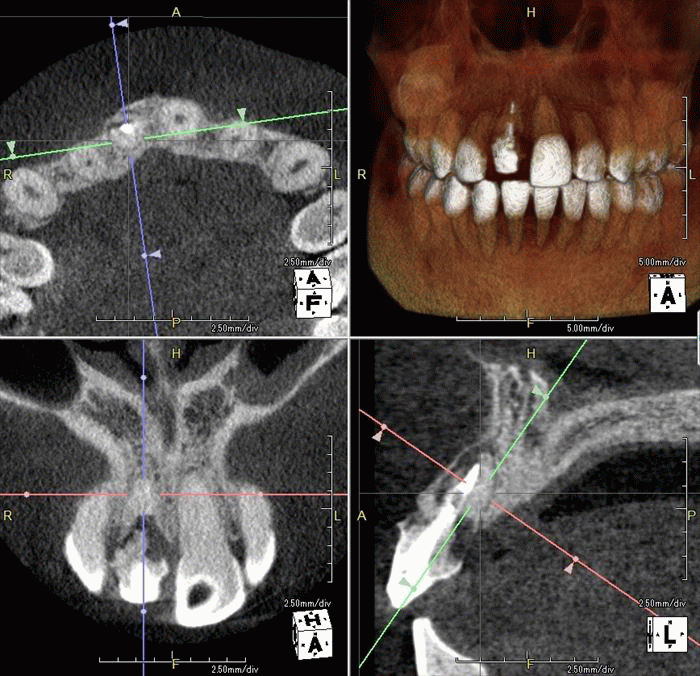

F・Kさんの初診時の状態です。

右上中切歯(右上1)に歯根吸収と炎症がありインプラント治療をご希望です。

過去に神経を取る治療(=根管治療)がなされており、残念ながら歯根の吸収が起こっています。

炎症がありますが抜歯時に唇側骨が保存出来るようであれば抜歯即時インプラント埋入オペが可能です。

ここからはドリリングを行い、インプラントを植えるためのインプラント床(しょう)を形成します。

深度ゲージを挿入して角度・深さを確認している場面です。

歯根の先端があった部分よりも口蓋側にインプラントの先端が位置するように、

明確な意思をもってドリリングする必要があります。

その面では抜歯即時埋入インプラントオペは難易度の高いオペといえます。